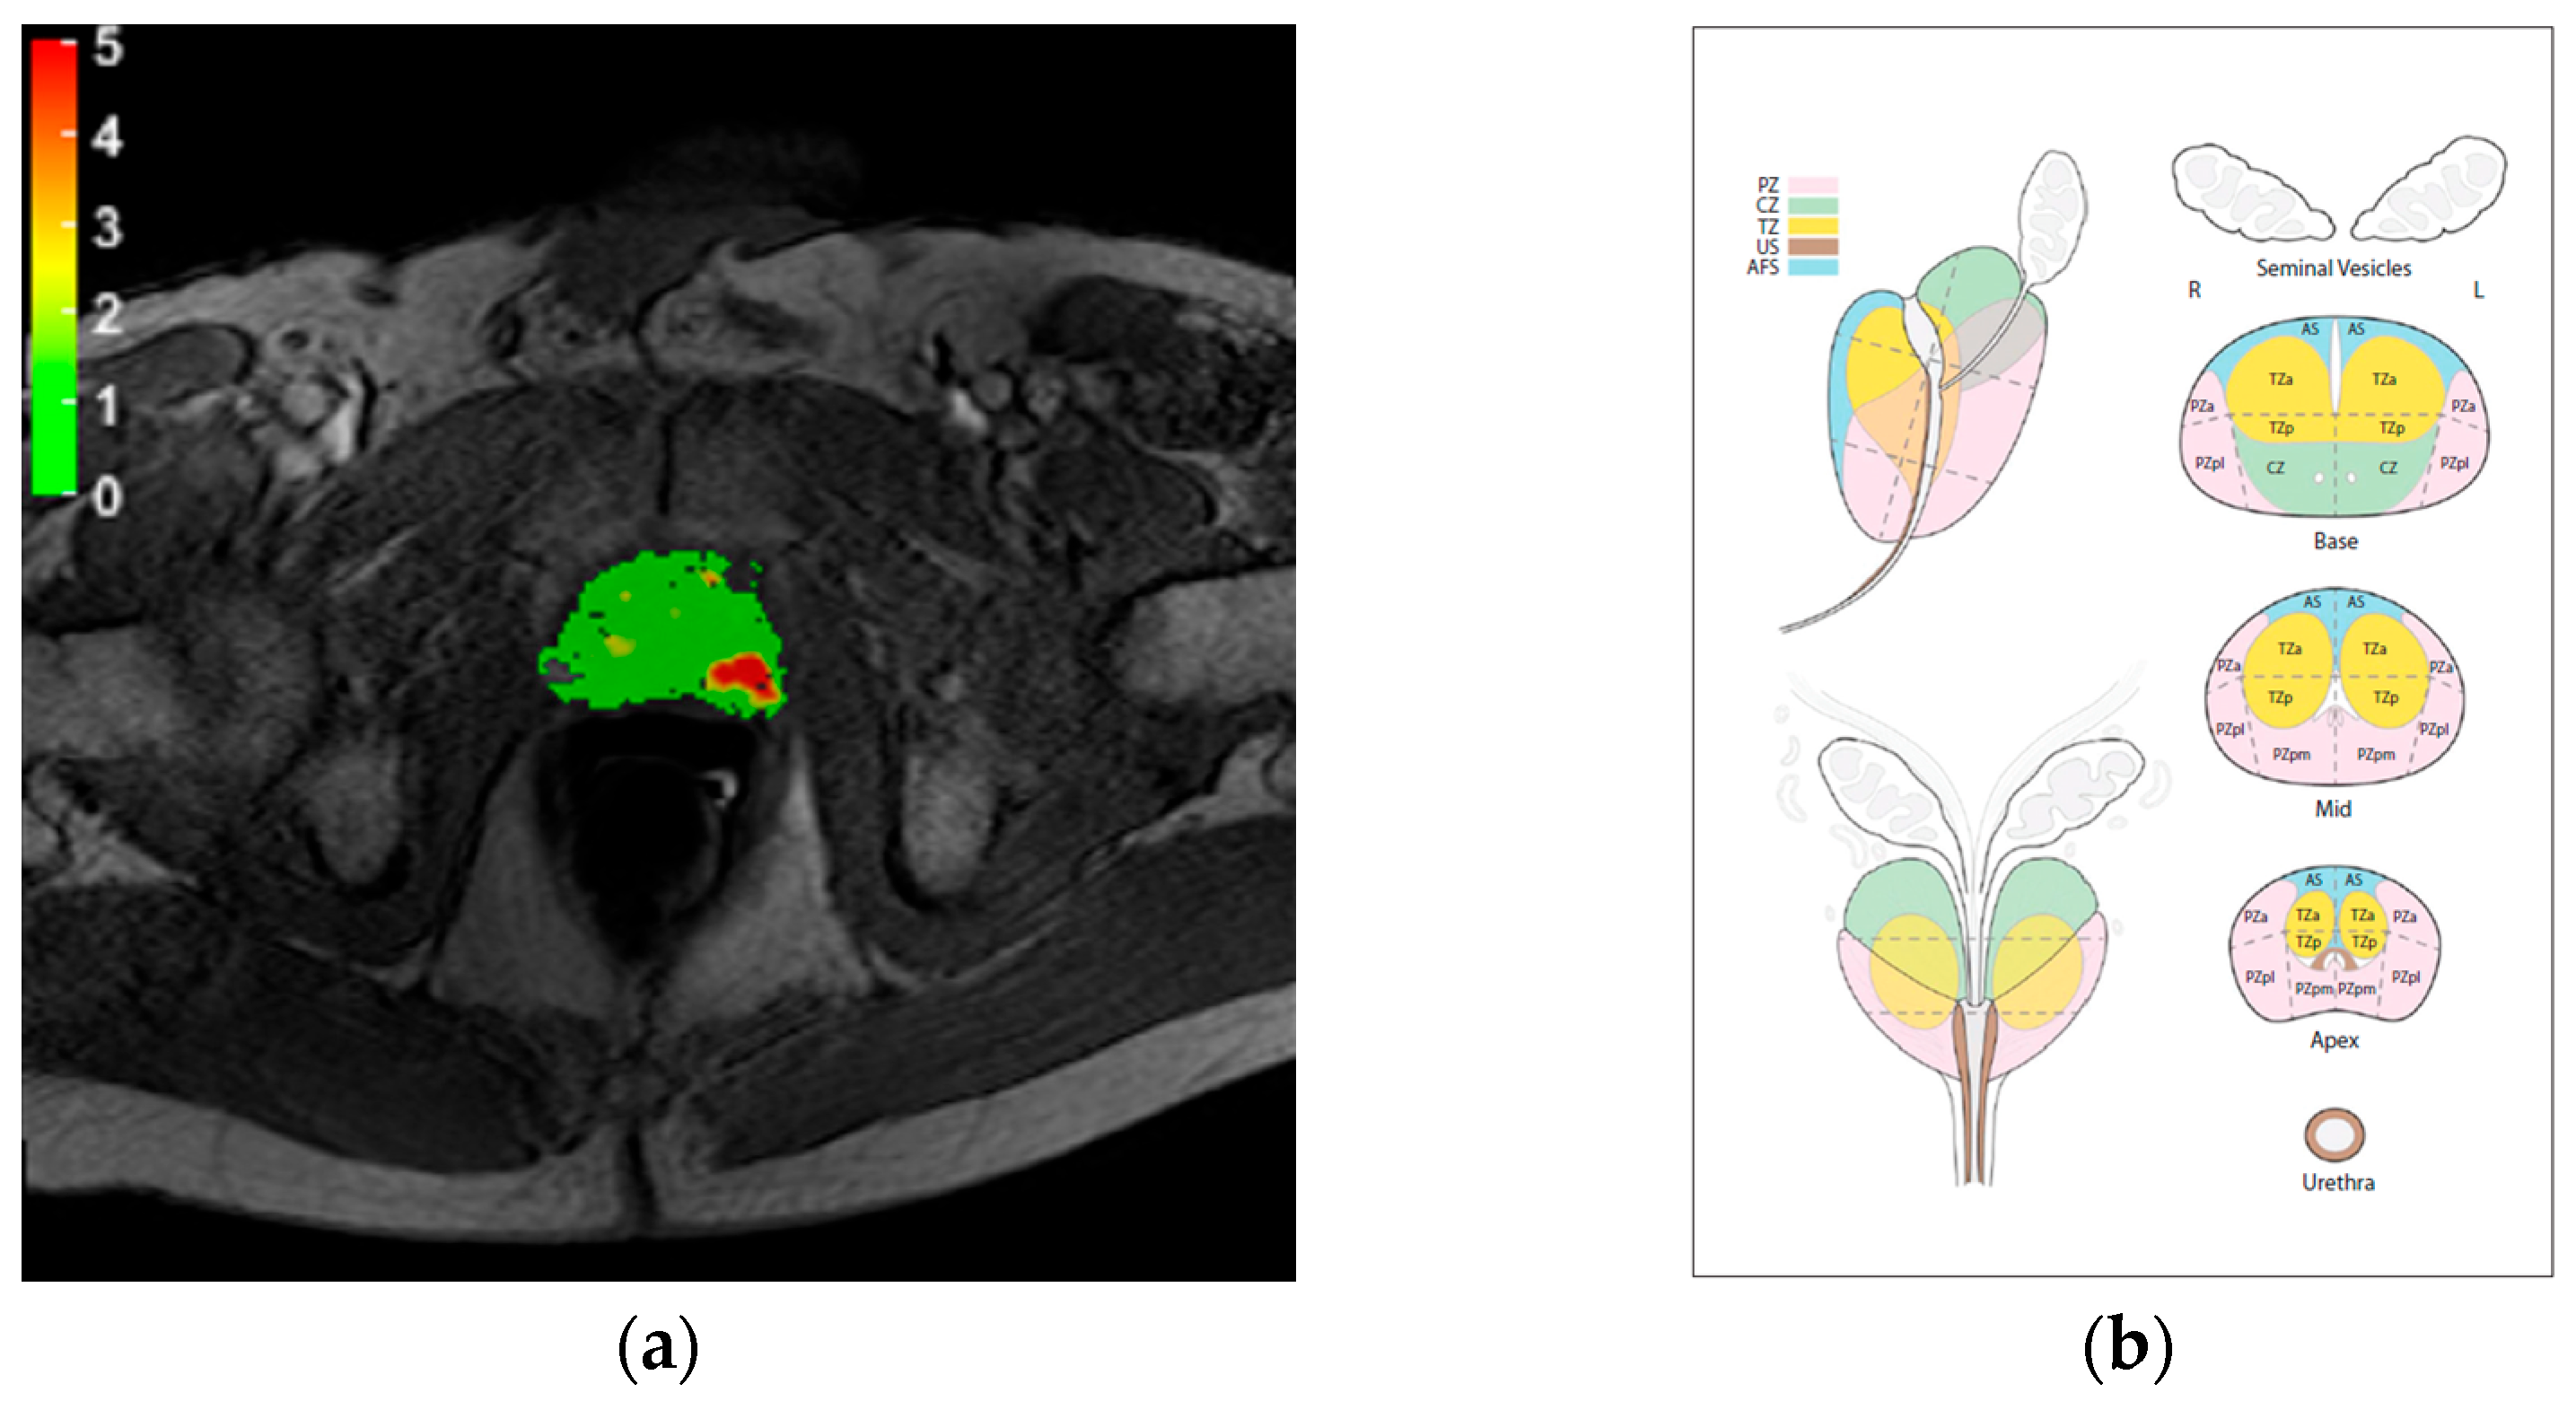

| Score | Assessment Category | MRDI Map Features |

|---|---|---|

| 0 | None (benign) | Continuous area with values below 1 |

| 1 | Very low (clinically significant cancer is highly unlikely to be present) | Continuous area with values between 1 and 2. Non-continuous area with values mostly below 2 |

| 2 | Low (clinically significant cancer is unlikely to be present) | Continuous area with values between 2 and 3. Non-continuous area with values mostly below 3 |

| 3 | Intermediate (the presence of clinically significant cancer is equivocal) | Non-continuous area with values between 2 and 4 |

| 4 | High (clinically significant cancer is likely to be present) | Continuous area with values between 3 and 4. Non-continuous area with values mostly above 4 |

| 5 | Very high (clinically significant cancer is highly likely to be present) | Continuous area with values above 4 |